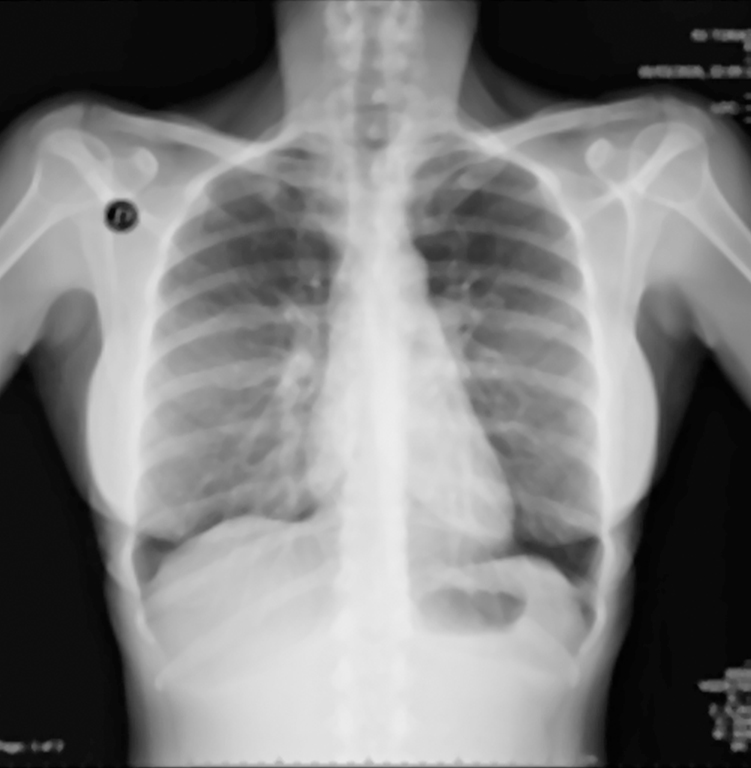

Similarly, the researchers participated in the presentation entitled, “The Authentication of Medical Images through a Hybrid Watermarking Method based on Hermite-Jigsaw-SVD,” where they discussed results from a robust method for watermarking medical images.

The doctors used the Steered Hermite transform (SHT), a spatial and frequency image decomposition technique inspired by the human vision system, to invisibly embed the watermark.

They also included singular value decomposition (SVD) in the proposal to obtain greater robustness of watermarks against attacks. They also used the Jigsaw transform to encrypt watermarks before embedding them in medical images. Finally, they used 40 X-ray images and the caduceus medical symbol as a watermark to evaluate the proposed watermarking method.

The results showed that the watermark is invisible to the human eye and is extracted without any loss of visual information. Furthermore, the marked medical images do not appear to have any significant visual alterations, preserving visual information for the patient’s diagnosis.

Furthermore, in tests involving attacks on a marked medical image, the results verified that the proposed method is robust and can stand up against common geometric and processing attacks (Gaussian noise, salt and pepper noise, median filter, JPEG compression, rotation, and translation), allowing the perceptible extraction of watermarks even in strong attacks where the marked medical image has lost a lot of information.